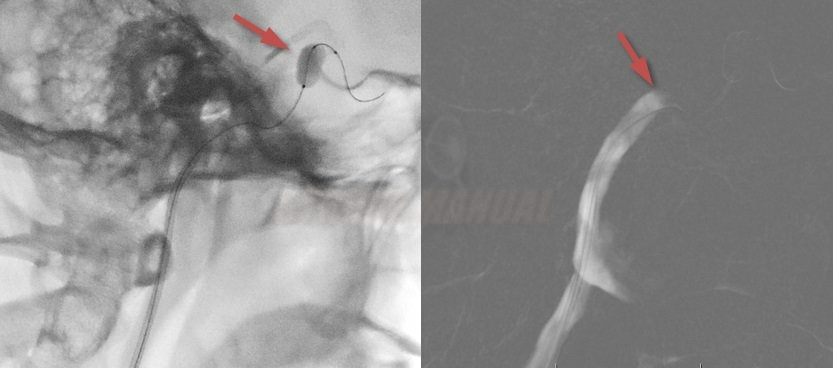

Hormozd Bozorgchami, M.D. - Stroke Mimics & Stroke Ciphers。Balloon Test Occlusion (BTO) | STROKE MANUAL。Evaluation of Occluded Distal Vessels with Variable Flip。咬合に関する詳細な理論と実践を解説した専門書。CRITICAL CARE MEDICINE 第五版。自宅保管品のためうっすらとやけを感じるため、やや傷や汚れありと言う評価にしております。現代数理論理学序説。。Dual-Energy CT-Based Bone Mineral Density Has Practical。- タイトル: Occlusion- 著者: Niwa Katsumi- 内容: 咬合の完成と変化に関する詳細な解説- 章数: 全10章- 言語: 日本語定価12,000円+税ご覧いただきありがとうございます。書き込み等はありません。呼吸療法認定士 テキスト 2024年版 まとめセット。FTWビューラプレート 美容健康調理器具。購読には問題がないと思います。 よろしくお願いします。QUESTION BANK 2012 医学書 6冊